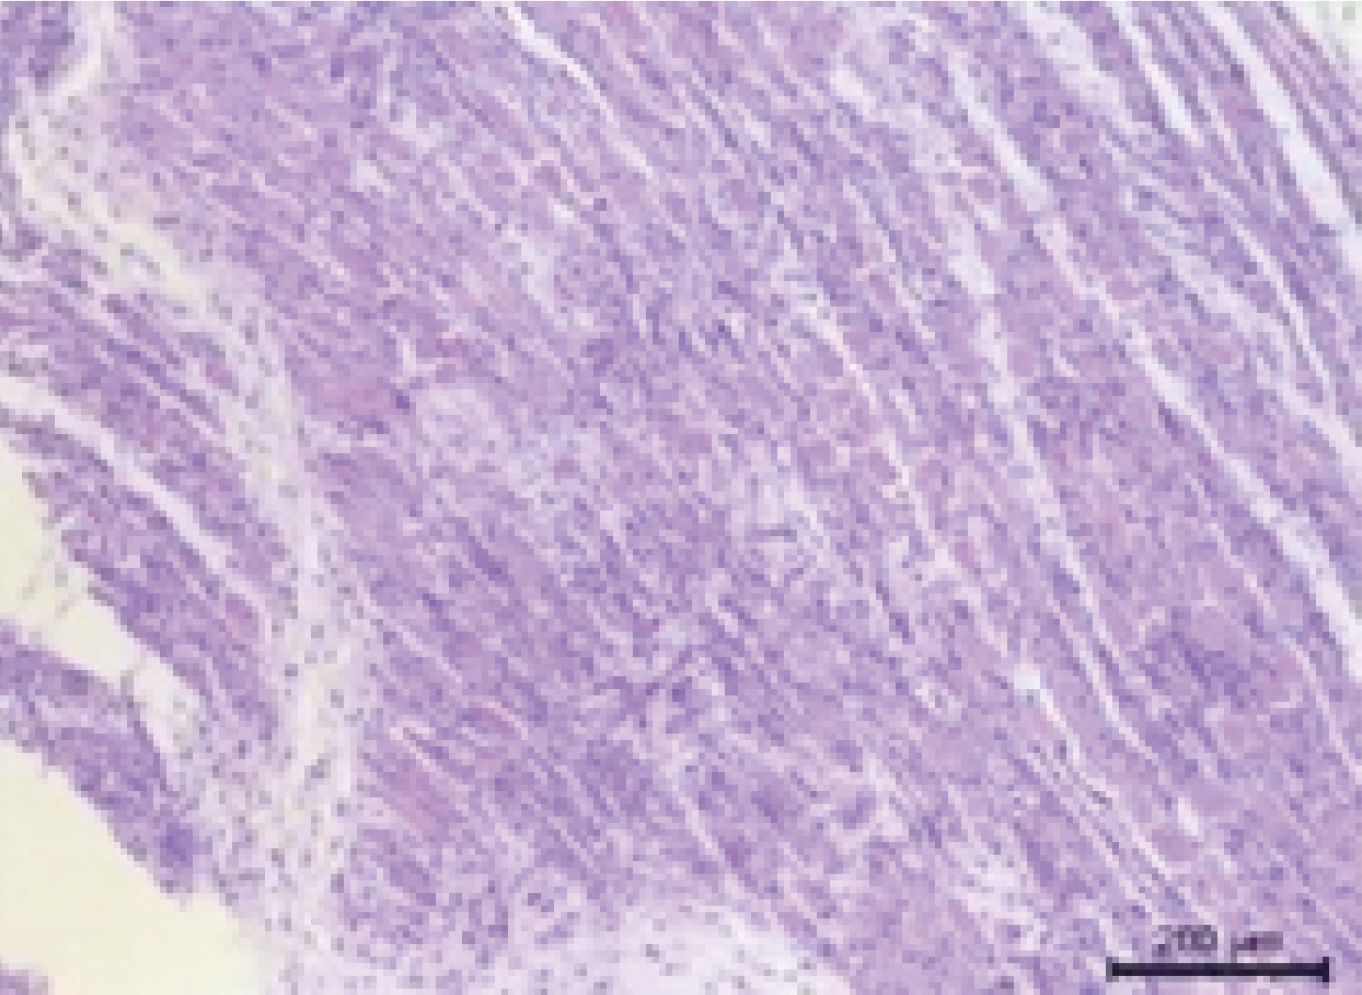

Pathological Criteria:

The vagina of model animals shows mucosal erosion, underlying edema, accompanied by extensive scattered inflammatory cell infiltration.